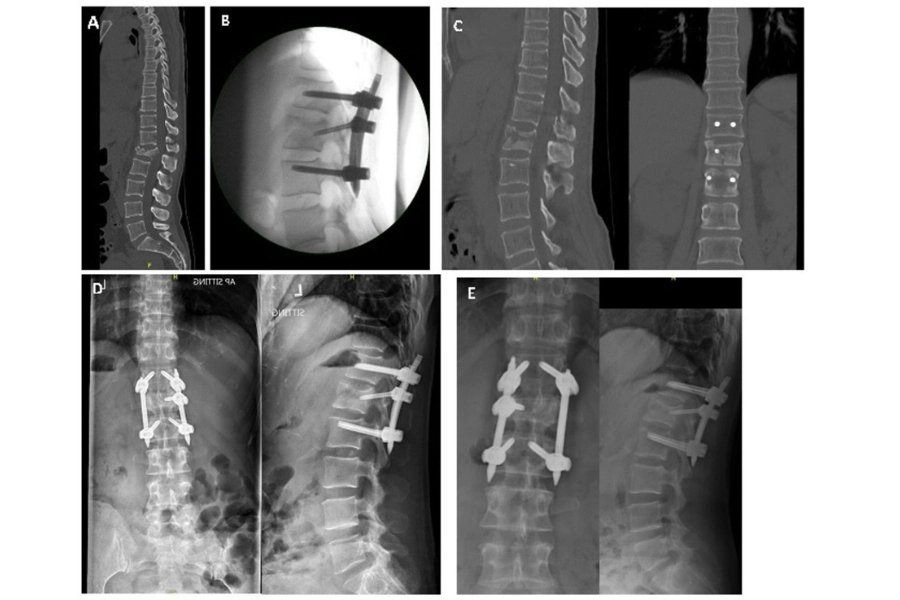

(A) Передопераційна комп’ютерна томографія (КТ), сагітальна проєкція.

(B) Інтраопераційна корекція: рентгенограма в сагітальній проєкції.

(C) Негайна післяопераційна комп’ютерна томографія (КТ), сагітальна та корональна проєкції.

(D) Контрольне обстеження через 6 місяців: передньо-задня та бокова проєкції.

(E) Контрольне обстеження через 2 роки: передньо-задня та бокова проєкції.